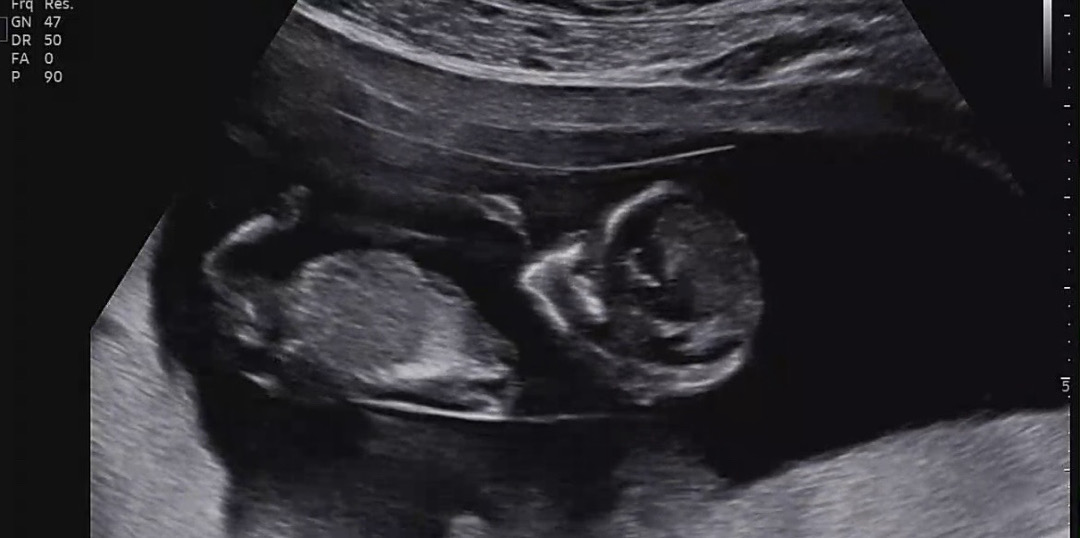

12주 1일 일란성 쌍둥이 각도법 봐주세용🥹

22개월 남아 키우고 있는데 지금 쌍둥이 임신중이에요~ 일란성이라 두아이 성별이 똑같아서 너무 두근두근합니다.. 각도법봐주세용 🥹🥹